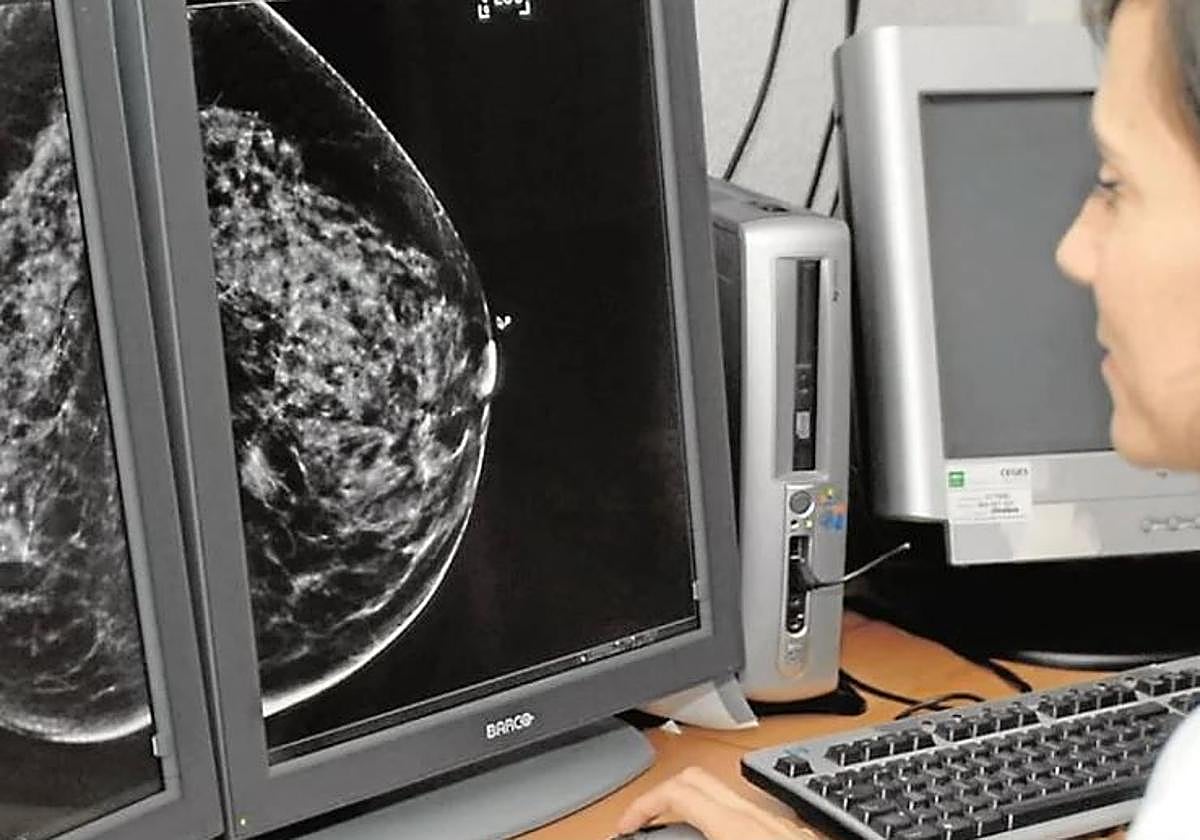

Actualmente, cuando se realiza una mamografía a una mujer dentro del programa de cribado del cáncer de mama existen tres posibles diagnósticos: negativo, positivo y lesión posiblemente benigna. En el caso de diagnósticos negativos, las pacientes son informadas del resultado; en el caso de diagnósticos positivos, las mujeres son igualmente informadas y derivadas para nuevos procedimientos pero, en los casos en los que se detectan lesiones posiblemente benignas las mujeres pueden no haber sido informadas de que su caso sigue un procedimiento clínico con supervisión médica, según explica la Junta.

La consejera ha indicado que, en estos casos, hasta tres radiólogos analizan las imágenes y, en función de los factores de riesgo de cada paciente, deciden el tiempo que ha de transcurrir para la segunda prueba. Las pacientes, que viven ajenas a estas circunstancias, reciben al cabo de meses o de un año una llamada que no esperan para esa segunda cita -fijada por el radiólogo- «y sienten alarma, intranquilidad y angustia».